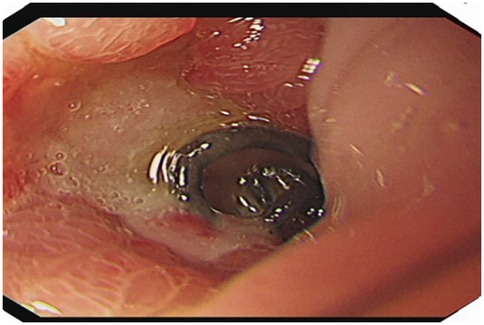

A 51-year-old male patient was admitted to the Department of Gastrointestinal Surgery in September 2020, presenting with “melena for one week and sudden abdominal pain for 11 h”. The patient had no significant medical history. Physical examination revealed right upper abdominal muscle tension, accompanied by tenderness and rebound pain in the same region. Laboratory tests indicated severe anemia (hemoglobin: 57 g/L), while tumor markers, including alpha-fetoprotein (AFP), carcinoembryonic antigen (CEA), carbohydrate antigen 199 (CA199), and carbohydrate antigen 724 (CA724), were within normal ranges. Computed tomography (CT) findings suggested gastrointestinal perforation. Consequently, the patient underwent surgical repair of a perforated duodenal bulb ulcer, followed by medical management with proton pump inhibitors. However, the patient failed to adhere to follow-up recommendations after discharge. In March 2021, the patient was readmitted due to “dizziness and fatigue for two days”. Laboratory tests revealed critically severe anemia (hemoglobin: 35 g/L). Gastroscopy demonstrated congested and erythematous gastric antral mucosa, pyloric deformity, and an ulcer on the anterior wall of the duodenal bulb with luminal narrowing, preventing endoscopic passage. Residual sutures and minor bleeding were observed (no biopsy was performed). Abdominal CT revealed thickening and irregularity of the gastric antrum and duodenal bulb walls, with no evidence of lymphadenopathy or masses (Figures 1, 2). Given the patient's recurrent duodenal bulb ulcer bleeding with stenosis and failure of conservative medical treatment, a laparoscopic distal gastrectomy (including resection of the bulb ulcer scar tissue) with gastrojejunostomy was performed. Postoperative pathological examination confirmed poorly differentiated adenocarcinoma in the anterior wall of the duodenal bulb, consistent with malignant transformation of the ulcer. The tumor, which measured 2.5 × 1.5 × 1.5 cm, is approximately 2 cm from the distal resection margin, with full-thickness invasion of the duodenal wall and extension into surrounding adipose tissue (Figures 3, 4). Intravascular cancer thrombi and perineural invasion were identified. Metastatic carcinoma was detected in six lymph nodes, and local mesenteric tissue infiltration was observed. Immunohistochemical staining results were as follows: CK7 (+), S-100 (nerve tissue +), CK20 (partially +), Ki67 (+ in approximately 45% of cells), Her-2 (−), and Villin (+). Mismatch repair proteins MLH1, MSH2, MSH6, and PMS2 were all expressed. Whole-body bone imaging showed no significant abnormalities. Postoperatively, the patient completed 8 cycles of CapeOX chemotherapy. Follow-up gastroscopy in September 2021 revealed multiple superficial ulcers in the isthmus and efferent loop. On May 13, 2024, follow-up gastroscopy identified an ulcer with stenosis in the isthmus (pathological biopsy confirmed no tumor recurrence), and abdominal enhanced CT showed no evidence of metastasis.